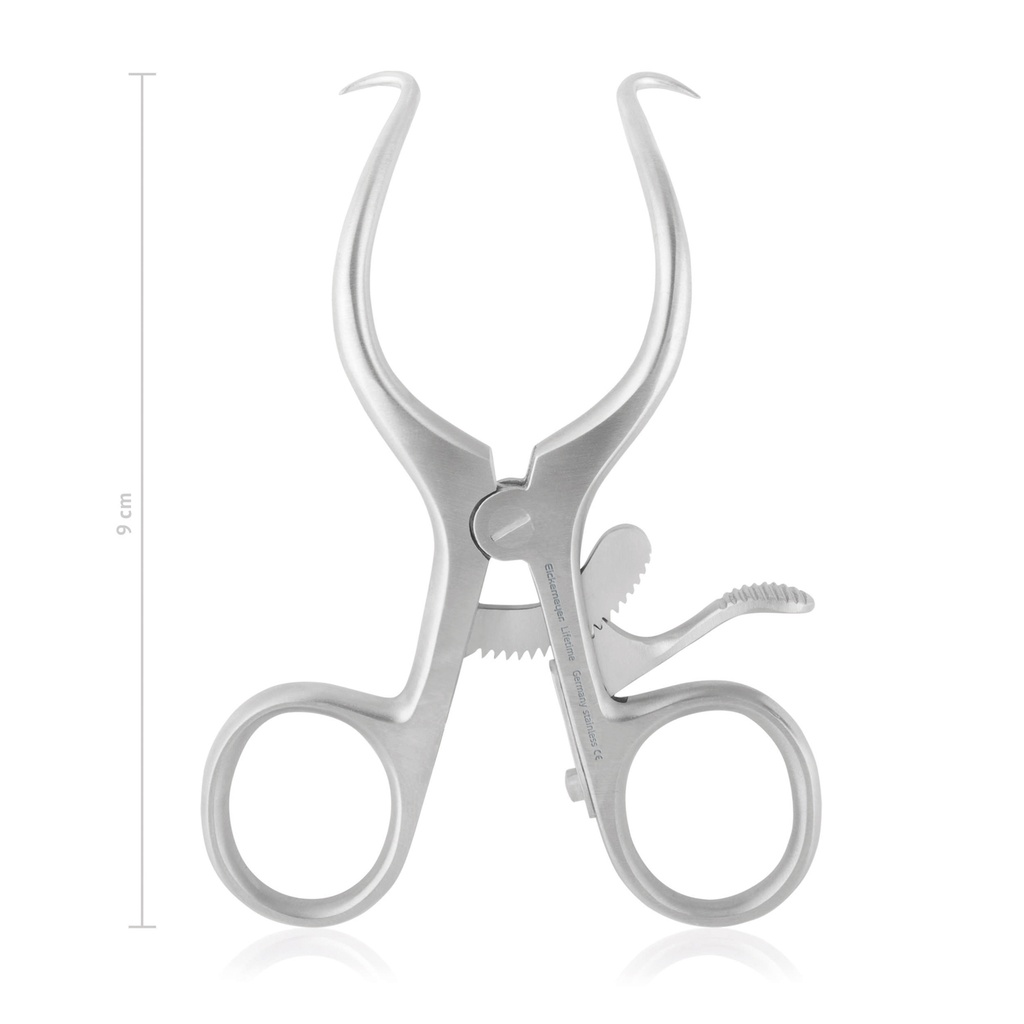

Wondsperder Gelpi, 9 cm, scherp

- Scherp

- Lengte: 90mm

- Zelfspannend